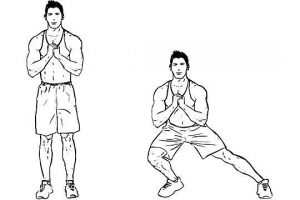

حرکت لانژ از پهلو

برای انجام این حرکت، بایستید و پاها را بهاندازهی عرض لگن از هم بازکنید و دستها را در جلوی سینه قرار دهید. سپس با حرکتی یکنواخت، یکی از پاهایتان را یکقدم به کنار بدن (در سمت چپ بدنتان) ببرید. درحالیکه کف پا روی زمین قرار دارد، زانو را خمکنید و باسن را به عقب حرکت دهید. وقتی یک انقباض شدیدی را درک باسن و ران پای دیگر احساس کردید، باید بایستید و سپس هردو پایتان بهجای قبلی خود برگردانید. این حرکت را ۱۰ تا ۱۲ بار تکرار کنید و سپس این حرکت را با پا دیگر انجام دهید. برای مقاومت بیشتر میتوانید یک توپ طبی را در جلوی سینه نگهدارید. این نوع ورزش به تقویت عضلات همیسترینگ، ابداکتورها یا دور شونده و عضلات چهار سر کمک میکند.